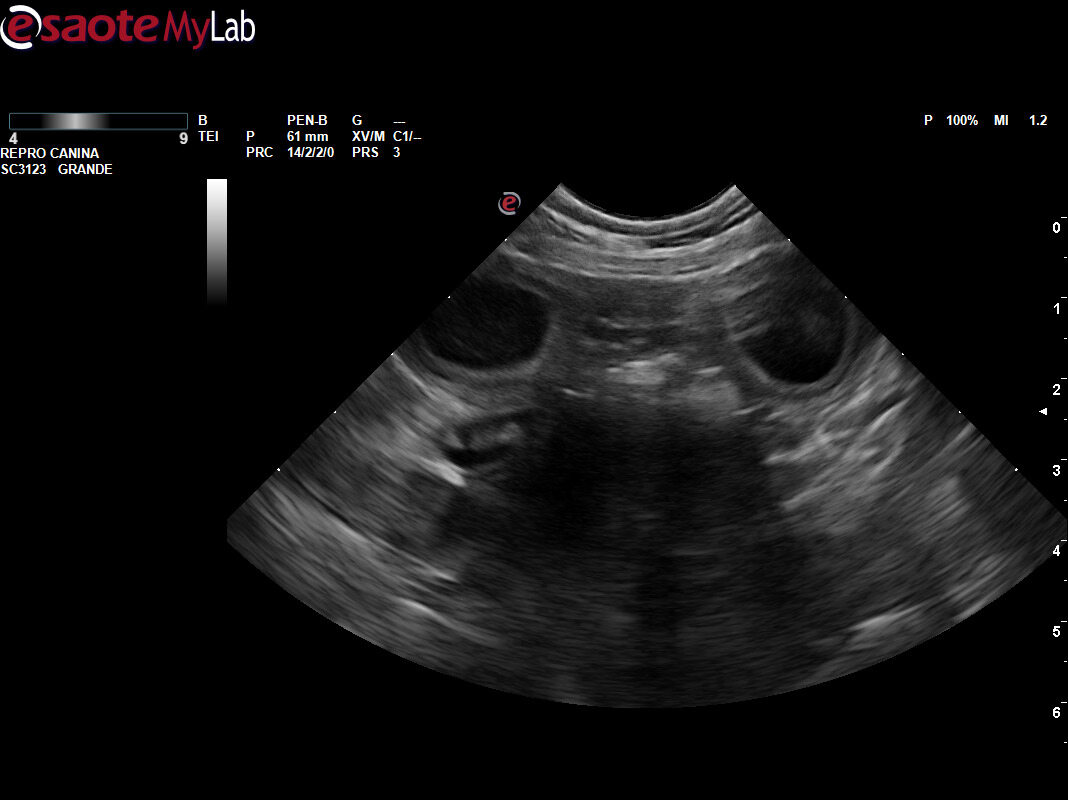

Este pasado viernes 11 de Abril hicimos la ecografía de confirmación de embarazo a Yis de Usurbe, una de nuestras hembras reproductoras 100%DDR

Los cachorros se espera que nazcan el fin de semana del 16 al 18 de Mayo de este 2025.

La lista de RESERVAS todavía cuenta con UN MACHO DISPONIBLE, aunque ya anticipamos que ésta será una Camada numerosa por lo visto en las imágenes.

En dos semanas, repetimos ecografía de control.